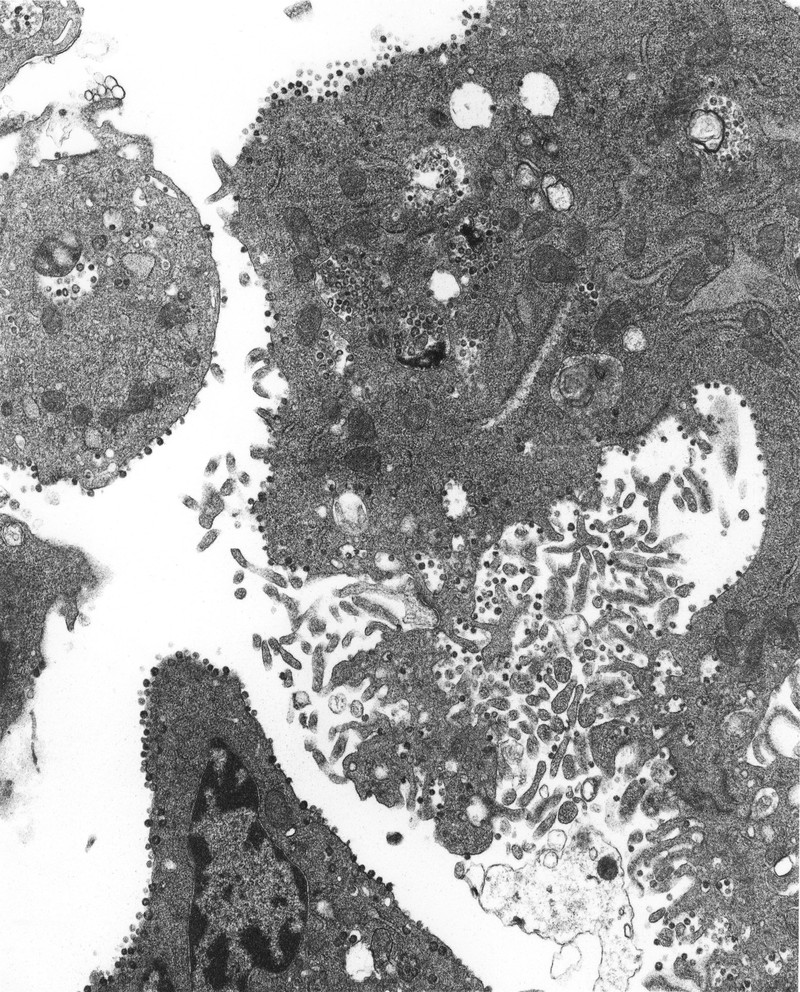

Mikrograf elektron bagian tipis dari virus corona yang tumbuh di dalam sel. Foto: John Nicholls, Leo Poon dan Malik Peiris, University of Hong Kong (Twitter/@hkumed).